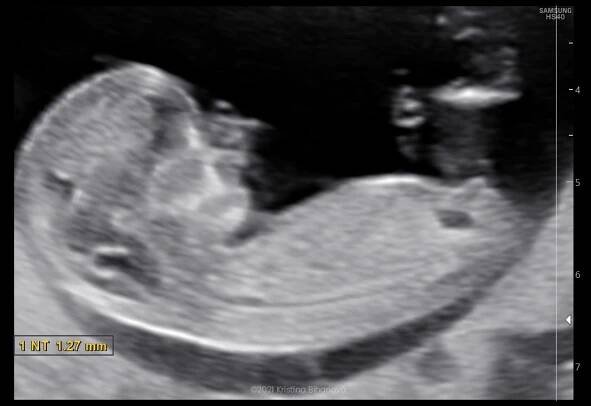

3D sonografia / 3D ultrazvuk - Prvý trimester - Celý plod

3D/4D ultrazvuk je vyšetření moderním přístrojem který nahradil původní jednoduchý systém vyšetření v dvojrozměrné projekci – přístroj pouze ukládal jednotlivé snímky z oblasti malé pánve.

3D ultrazvuk je lékařská ultrazvuková technologie, často používaný v porodnické ultrasonografii (během těhotenství), poskytující troj-dimenzionální obrázek plodu. Wikipedie